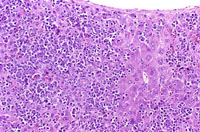

The liver is a relatively frequent site of infiltration by malignant lymphocytes, especially in strains with a high prevalence of lymphoma.

Infiltration of malignant lymphocytes in a liver from an adult mouse.

Severe infiltration of the liver by malignant lymphocytes. Hepatocytes visible in the lower right corner.